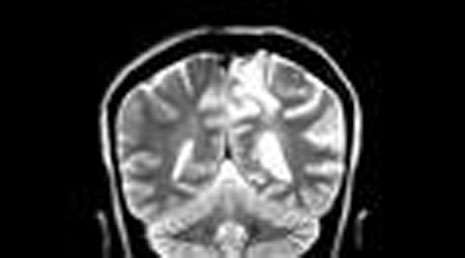

40. Mesial temporal sclerosis- temporal lobe epilepsy